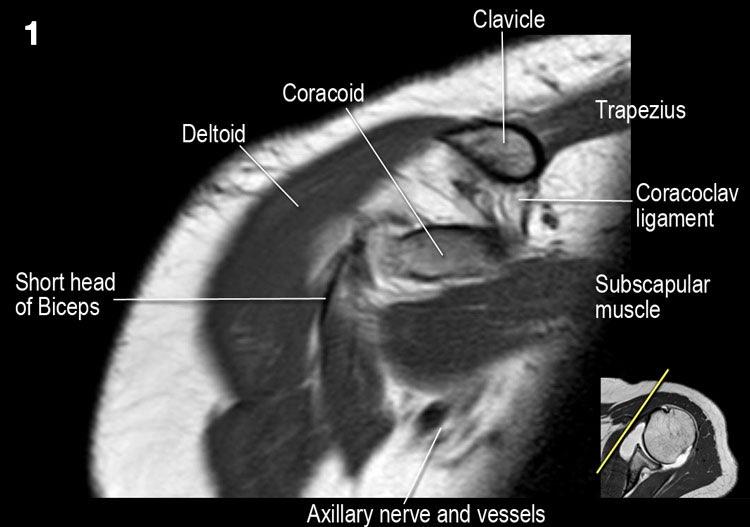

Giải phẫu mặt cắt vành và danh sách kiểm tra

- Lưu ý dây chằng quạ-đòn và đầu ngắn cơ nhị đầu.

- Lưu ý dây chằng quạ-mỏm cùng vai.

- Lưu ý thần kinh và mạch máu trên vai.

- Tìm kiếm hội chứng chèn ép cơ trên gai do gai xương khớp cùng-đòn hoặc dây chằng quạ-mỏm cùng vai dày lên.

- Đánh giá phức hợp sụn viền-gân cơ nhị đầu phần trên và tìm kiếm túi cùng dưới sụn viền hoặc rách SLAP.

- Tìm kiếm tràn dịch quá mức trong túi hoạt dịch dưới mỏm cùng vai và rách gân cơ trên gai.

- Tìm kiếm rách kiểu “rim-rent” của gân cơ trên gai tại chỗ bám của các thớ sợi trước.

- Đánh giá chỗ bám của dây chằng ổ chảo-cánh tay dưới (IGHL) vào xương cánh tay. Đánh giá phức hợp sụn viền-dây chằng phần dưới. Tìm kiếm tổn thương HAGL (bong điểm bám dây chằng ổ chảo-cánh tay tại xương cánh tay).

- Tìm kiếm rách gân cơ dưới gai.

- Lưu ý tổn thương Hill-Sachs nhỏ.